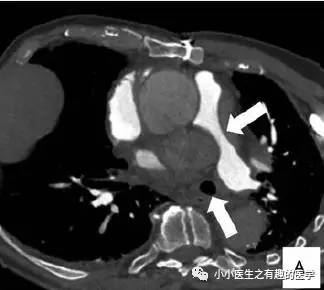

这么大一个血栓!需要你,我是一只鱼。

好大的一条血栓!

然而,最终做了手术,病理如下:

五颜六色的,好好看啊。然而,this is 肺动脉内膜肉瘤。

仔细看看,不对。

充盈缺损的地方,密度不均匀,并且,有强化,血栓里面没有血管,一般不会强化,所以,有可能是肿瘤。